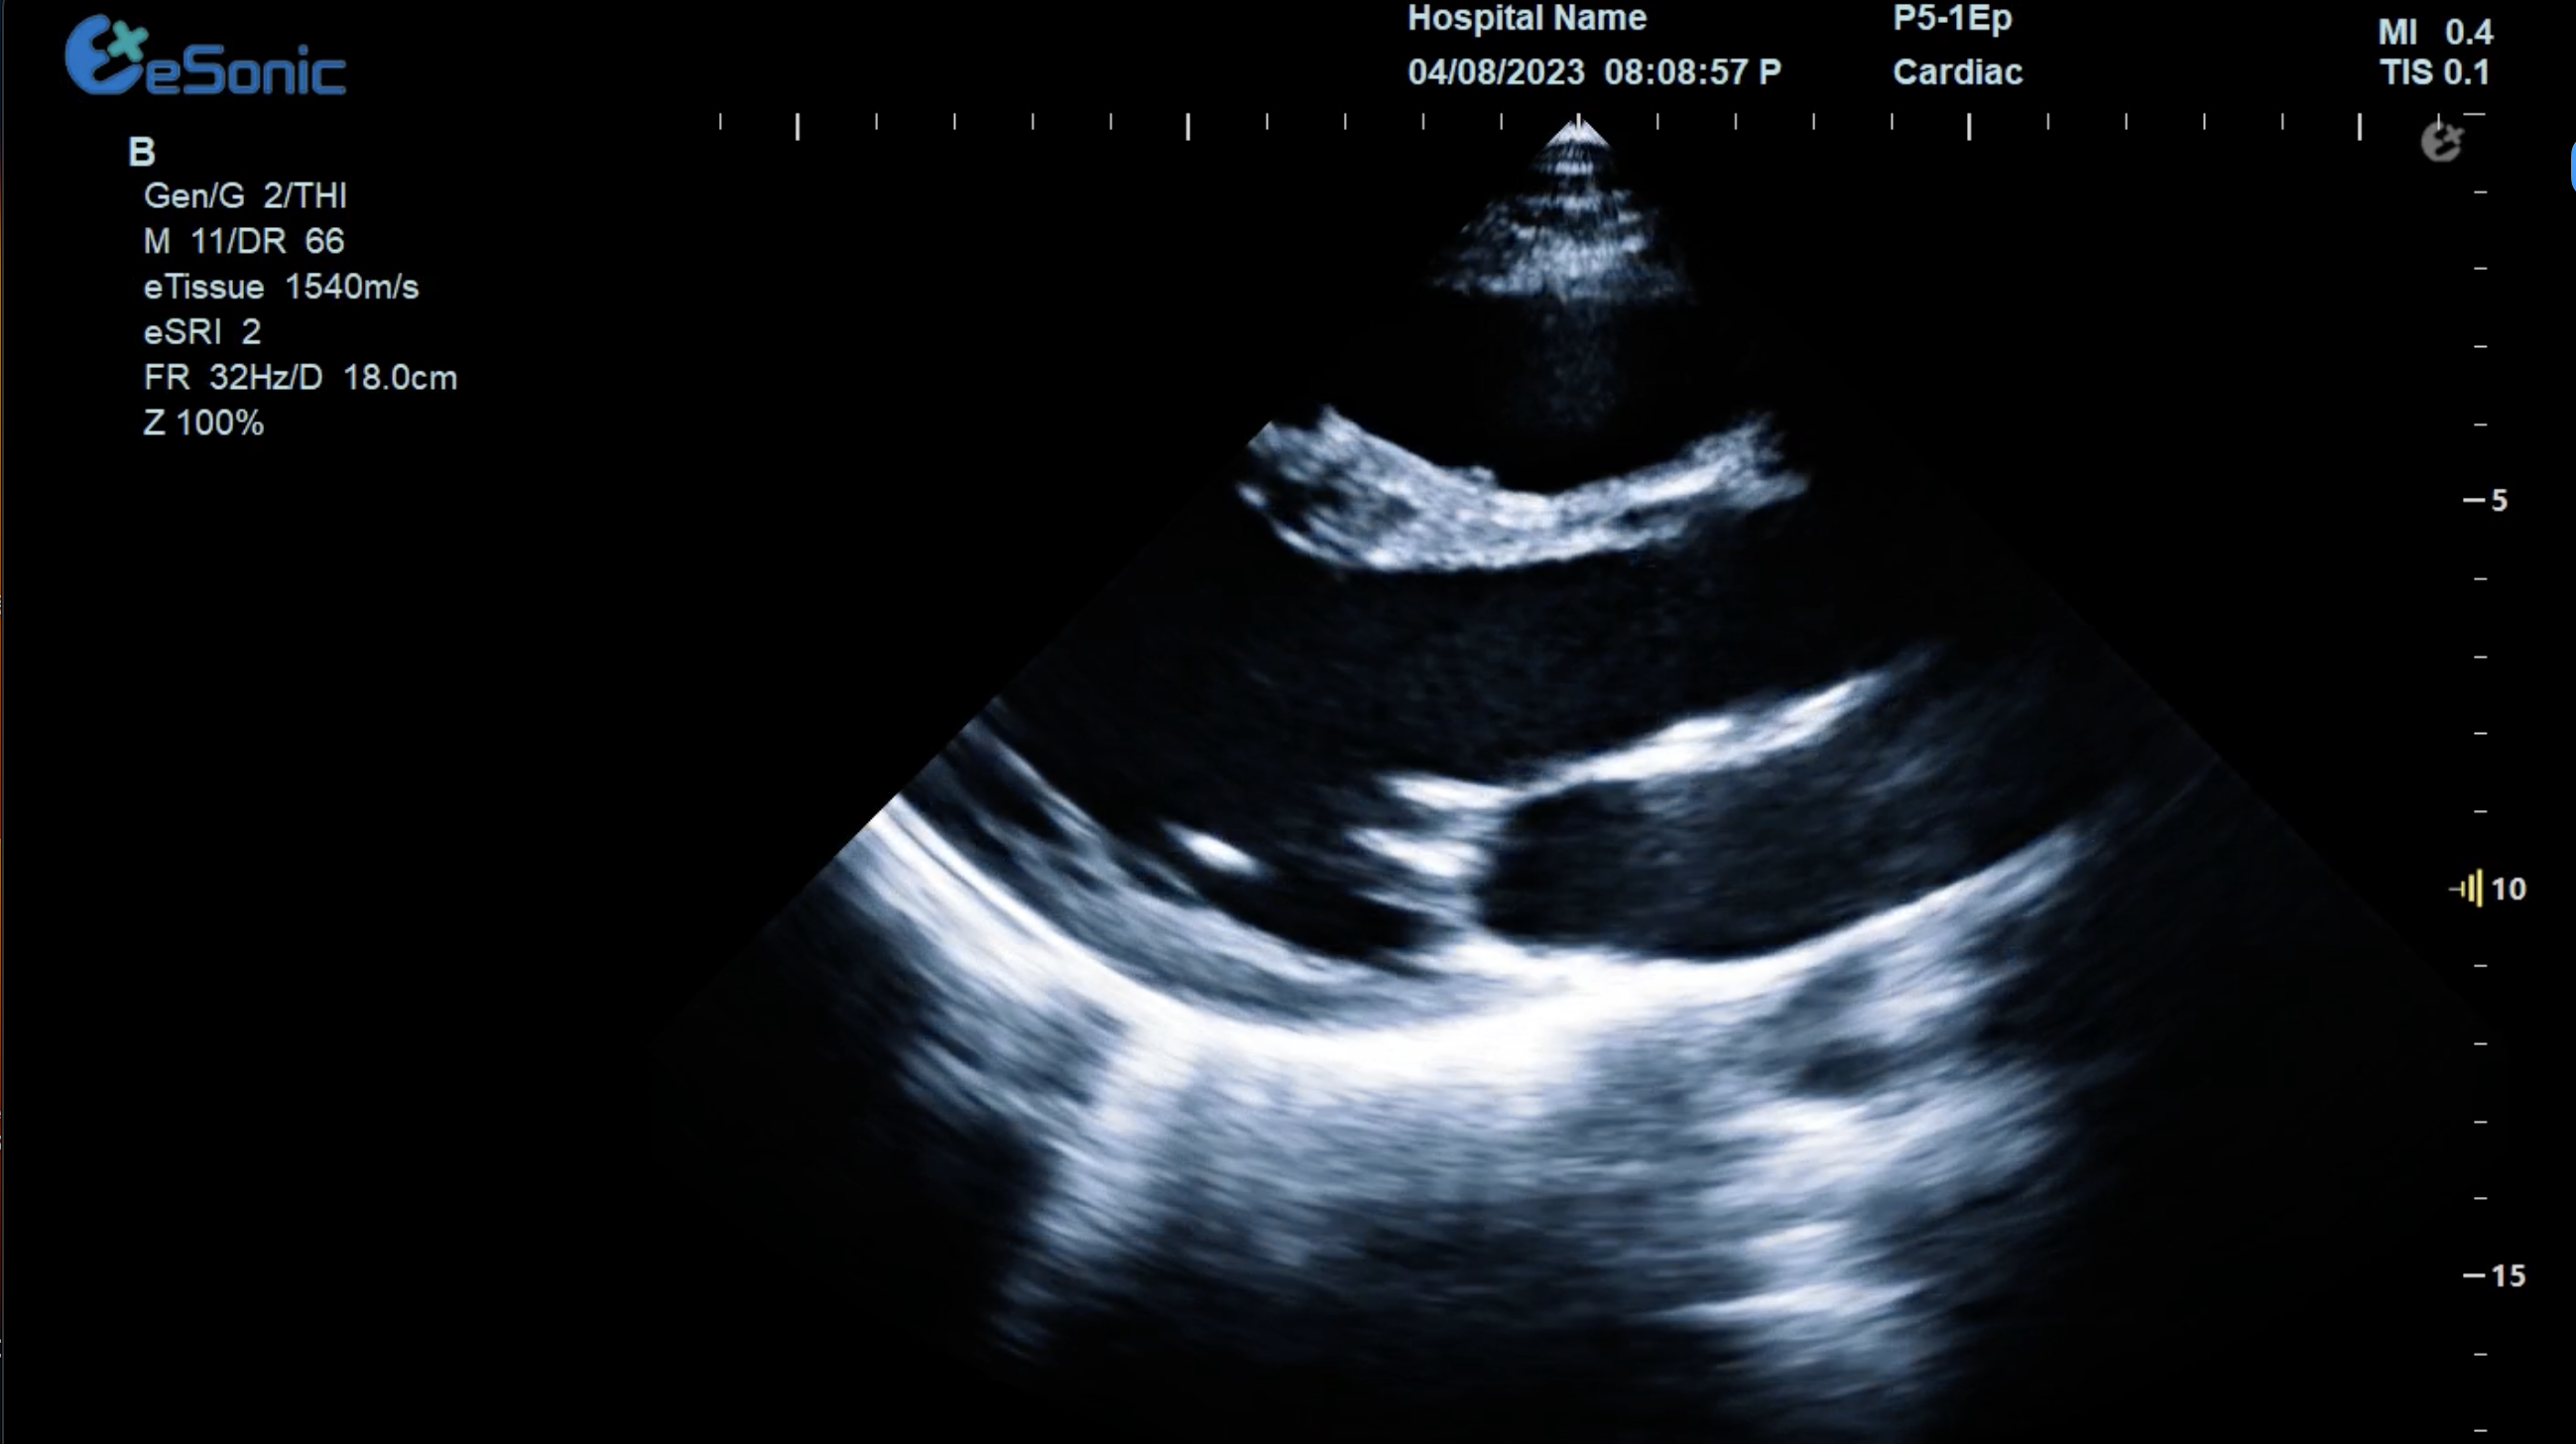

临床病例(一)

女性,68岁,临床诊断:冠心病

超声表现:左房大,左室壁运动幅度明显减低,以室间隔较明显;心包腔内见无回声区,右室前壁8mm,左室侧壁10mm。

冠心病、心包积液

重症心脏超声- FATE方案:

是重症病人循环管理推荐的目标导向超声评估评估方案之一,在此基础上扩展快速的下腔静脉超声检查,增加和完善容量状态和液体反应性的评估。

胸骨旁左心室长轴切面image.png

扫查方法:探头放在胸骨左缘三到四肋间或距胸骨2-3cm处,探头标记指向患者右肩大约9-10点位置

超声声像图:显示左房、左室、主动脉、右室、室间隔及后壁;同时,此切面可观察二尖瓣及主动脉瓣的形态及运动。

心尖四腔切面

扫查方法:探头放在心尖搏动处,使超声束由心尖向右上方指向心底。

超声声像图:显示左、右侧心房及心室、房室间隔;二、三尖瓣的形态及结构;心腔血流灌注、瓣膜返流等。